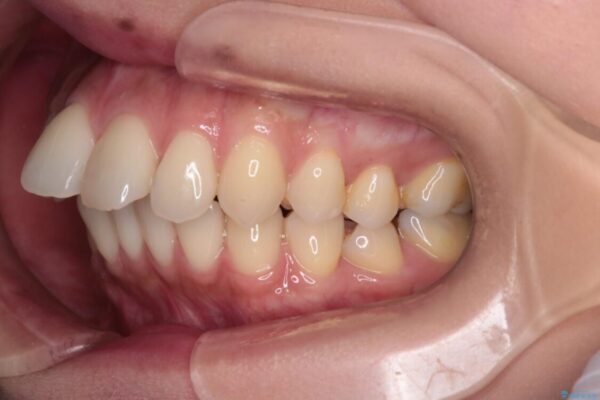

インビザラインにて抜歯矯正を行うと、高頻度で奥歯が咬み合わなくなります。

また、抜歯スペースに向けて奥歯が移動する際、必ず傾斜して移動するため、仕上がりの咬み合わせはワイヤー矯正と比べて明らかに劣ります。

抜歯スペースが閉じてからも咬みにくさ改善のためマウスピース矯正を継続するため、治療期間は長期化します。

治療途中

• 上顎前歯の突出を軽減 インビザラインによる抜歯矯正 治療途中画像